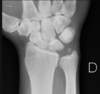

Cisto ósseo aneurismático

Acomete paciente jovem (fise aberta);

Localização excêntrica, aspecto em favo de mel no RX;

Pode ter reforço periosteal;

RM:lesão multicística; Septos + nível liquido-liquido (lesões dx diferencial: COS fraturado, COA, TCG ou osteossarcoma telangiectásico).

Primário ou Secundário à outros tumores: TCG, DF, Condroblastoma.